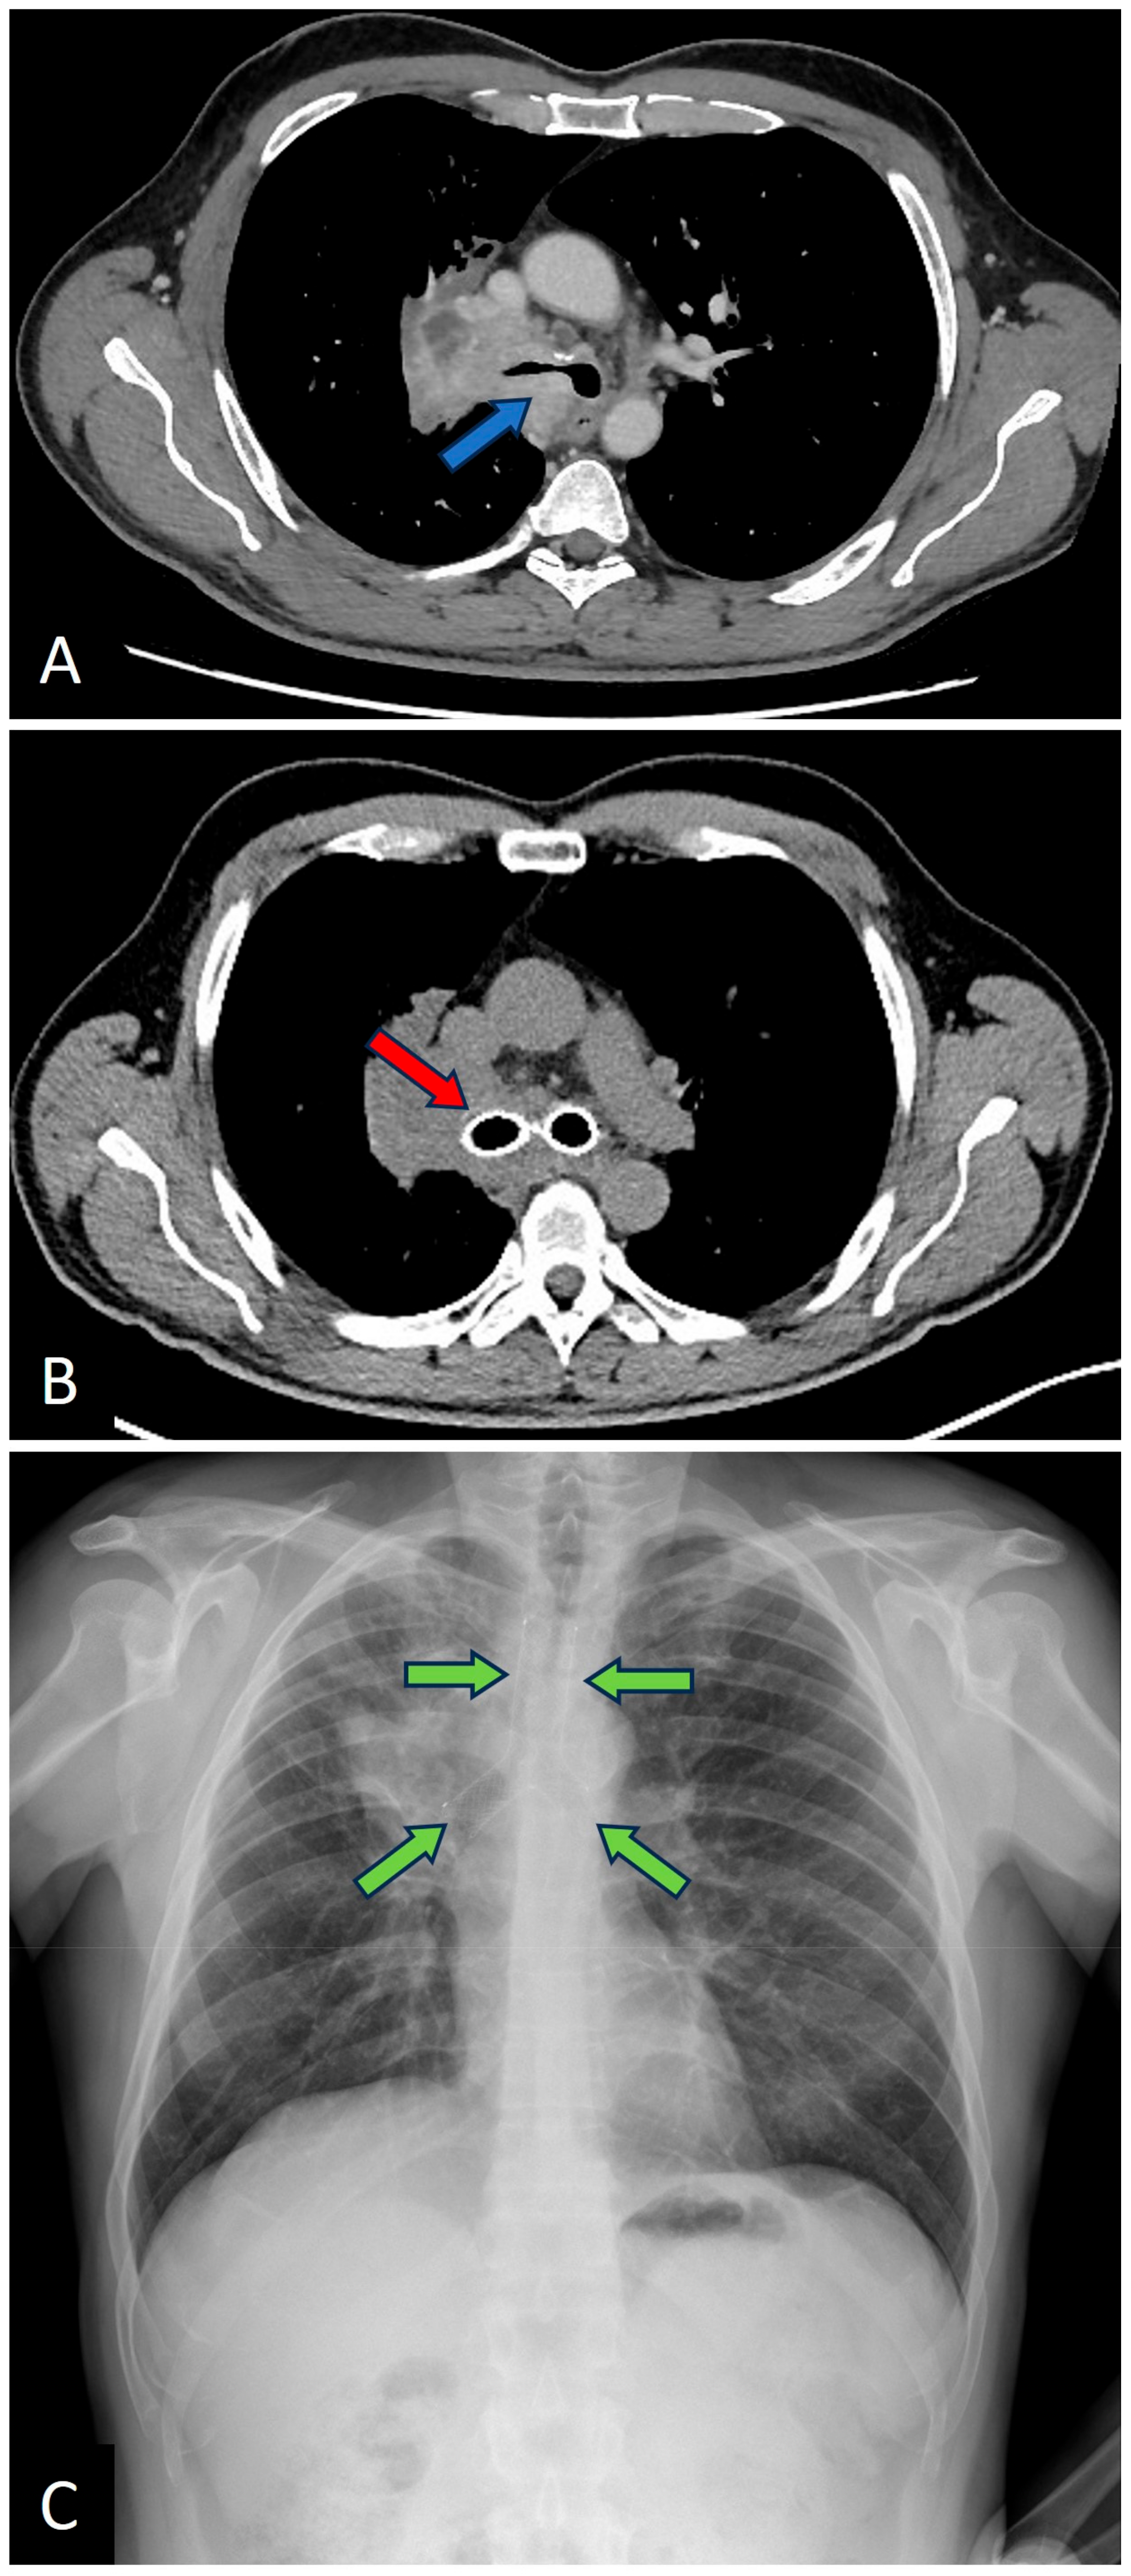

For illustration of the procedural outcomes, Figure 1 and Figure 2 show images of airway obstructions and the resulting therapeutic interventions performed on representative cases.

Figure 2. (A) Chest CT showing obstruction of the right main bronchus and carina (blue arrow); (B) Follow-up chest CT after Y-stent placement (red arrow); (C) Chest X-ray showing the same case (stent clearly visible, green arrows).